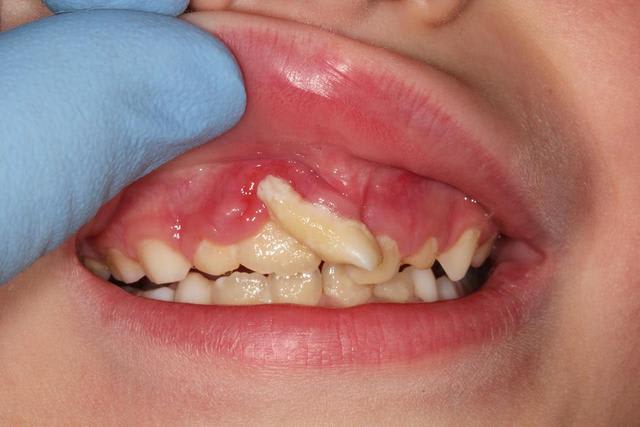

je suis dans le concours là ? ( je vous évite les clichés sur les postérieures,c'est à pleurer)

65 ans de sexe féminin ,2 paquets par jour.